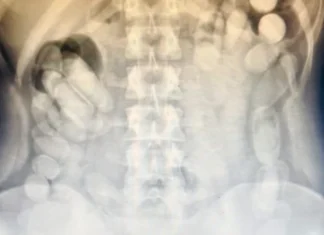

Narcotráfico: una mujer ingirió más de 100 cápsulas con cocaína

El peso final de la sustancia secuestrada alcanzó 1 kilo 388 gramos, cifra que confirma la gravedad y escala del intento de contrabando.